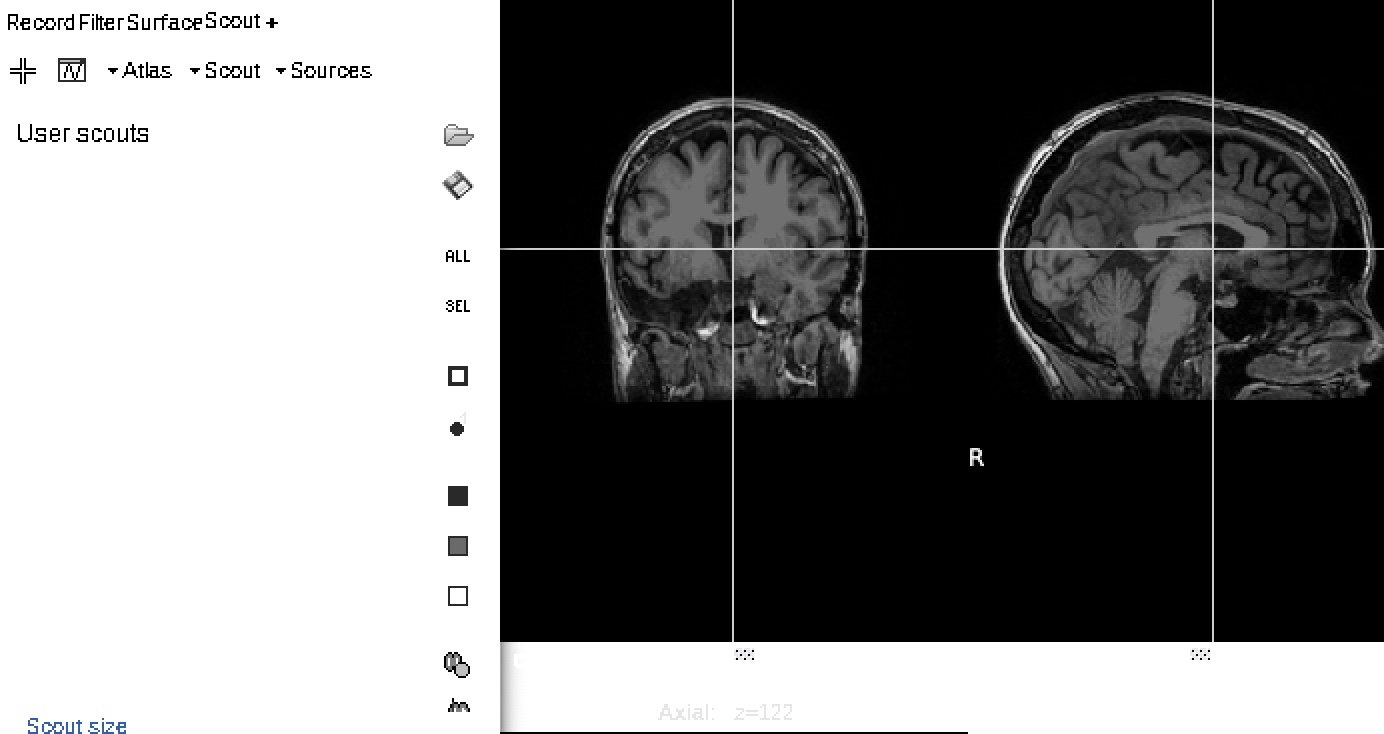

I am trying to run analyses on specific thalamic nuclei that I merged in my User Scout. Currently, this only seems to work when viewing them on the thalamic surface (image 1). However, the merged nuclei, as well as the thalamic atlas itself, do not appear in the Head model β†’ Scout tab (image 2).